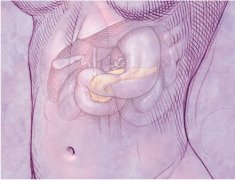

十二指腸炎是指發(fā)生于十二指腸的炎癥,分為原發(fā)性和繼發(fā)性兩種,原發(fā)性者也稱非特異性十二指腸炎。本病臨床癥狀缺乏特征性,主要表現(xiàn)為上腹部疼痛、惡心、嘔吐、嘔血和黑便,有時和十...